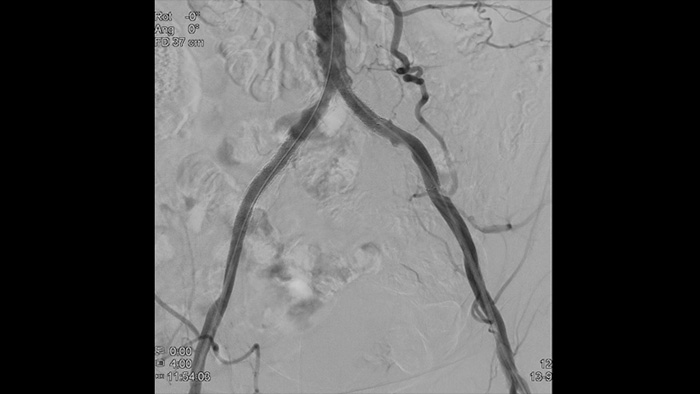

Nuestra suite vascular ofrece opciones de flujo de trabajo, herramientas de intervención especializadas y una amplia selección de dispositivos vasculares avanzados para mejorar la eficiencia del procedimiento y redefinir los resultados para sus pacientes con enfermedad aórtica. Respaldan cada paso del procedimiento, a medida que decide, guía, trata y confirma los resultados del tratamiento.

Con Philips Azurion se ha logrado un gran avance en la mejora del flujo de trabajo, lo que da como resultado una eficiencia probada. Con el número cada vez mayor de pacientes con enfermedades aórticas, Azurion ofrece una serie de innovaciones de flujo de trabajo diseñadas para ayudar a los equipos de cirujanos vasculares a trabajar de manera eficiente y constante, mientras mantienen un enfoque único en el paciente y administran la dosis de radiación durante las intervenciones.